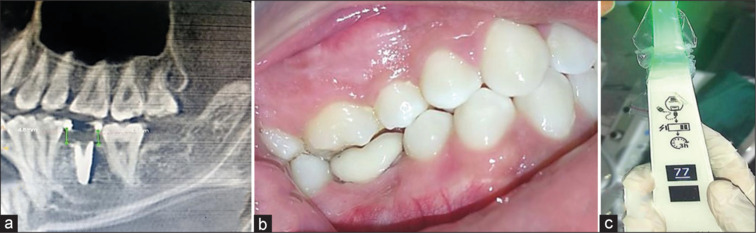

Materials and methods: Fourteen patients were included in this study, of which seven patients were under Group A (delayed) and seven patients were under Group B (immediate). The clinical evaluation was done at baseline, 3 months, and 6 months which includes plaque scores, bleeding on probing, and probing depth. Implant stability was tested by resonance frequency analyzer (implant stability quotient), and radiological evaluation of crestal bone loss was done by cone-beam computed tomography preoperatively and after 6 months.

Results: In this study, there was no statistically significant difference (P > 0.05) in the clinical parameters (plaque index, bleeding on probing, and probing depth) and radiological outcomes within the groups at baseline, 3 months, and 6 months. The implant stability quotient and crestal bone loss between Groups A and B showed a statistically significant difference at baseline and 6 months, wherein there were higher implant stability and decreased crestal bone loss in Group A when compared to Group B.